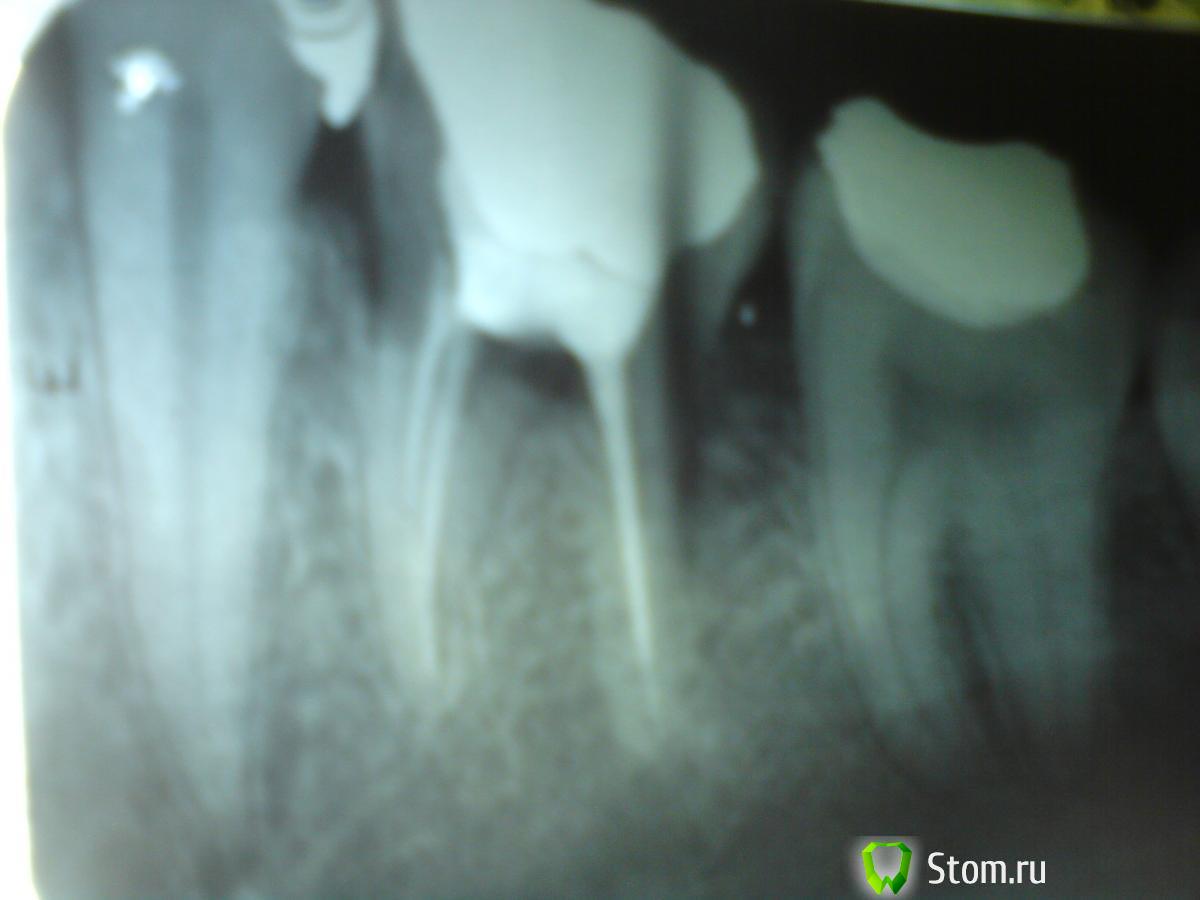

Alegon Опубликовано 24 апреля, 2012 Поделиться Опубликовано 24 апреля, 2012 Здравствуйте, два независимых стоматолога сказали, что лечить не получится, нужно рвать. Зуба жаль, да и возраст ещё вроде бы не тот, чтобы терять. Поэтому решил обратиться к форуму, чтобы окончательно убедиться в том, что выхода нет, или наоборот разубедиться. Буду благодарен Вашим ответам на два вопроса, которые меня волнуют: 1) Возможно ли лечение? Или случай безнадежный?2) Насколько вредно промедление с вырыванием? Стоит не тянуть с этим, или можно ждать пока зуб не потревожит? Снимок в приложении. Сделан в декабре 2011. Ссылка на комментарий

Мартовский Опубликовано 24 апреля, 2012 Поделиться Опубликовано 24 апреля, 2012 1) Случай безнадёжный2) "Резать не дожидаясь перитонита" 1 Ссылка на комментарий

igorstom Опубликовано 27 апреля, 2012 Поделиться Опубликовано 27 апреля, 2012 За себя скажу. Я бы не взялся за сохранение данного зуба. Ссылка на комментарий

dok1 Опубликовано 27 апреля, 2012 Поделиться Опубликовано 27 апреля, 2012 И лучше не тянуть. Может уменьшиться объём кости, что приведёт к трудностям при подготовке к имплантации. Ссылка на комментарий